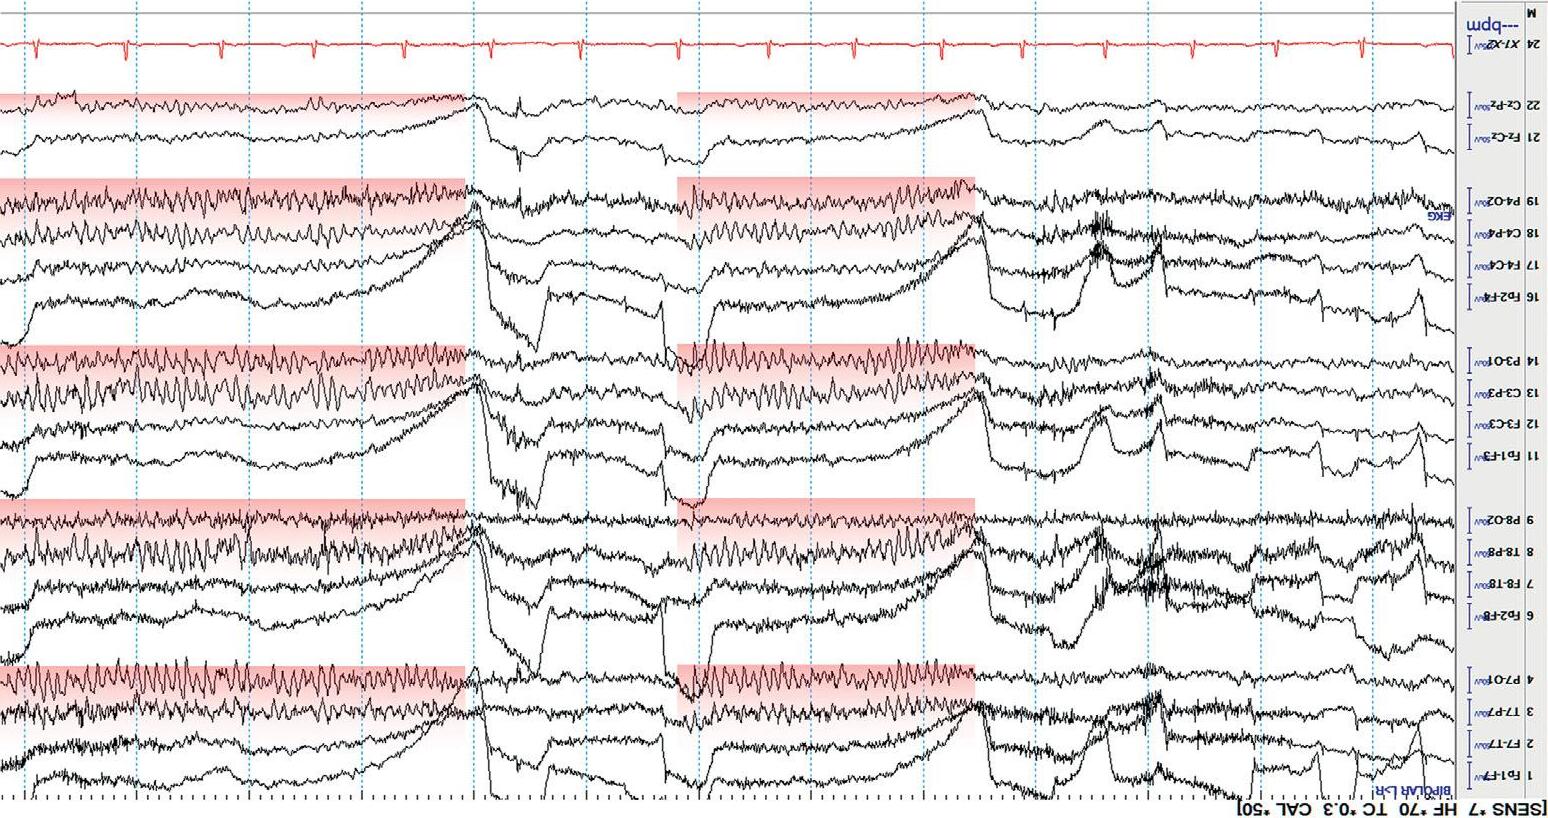

Lookforthe alpharhythm(posteriordominantrhythm,PDR).Thisisthe 8.5 – 13Hz(alpharange)rhythm,maximalintheposteriorheadregions, thatattenuateswitheyeopening(anindicationofreactivity).Thealpha rhythmisanobviousfeatureofnormalwakefulnessandisbestobserved aftereyeclosureintheoccipitalchannels(O).Loweramplitude beta activity occursanteriorly.Anyintrusionofthetaordeltaactivityduringfull wakefulnessisusuallyindicativeof anabnormality.Furthermore,theamplitudeofthebackgroundactivityshouldnormallydecreasefromposterior (O)toanterior(Fp).Thisiscalledthenormal anterior –posterior(AP) gradient .Additionally,therewillbeartifactfrom eyeblinks and muscle activityinthefrontalisandtemporalismuscles. Figure1.6 showsanEEG duringnormalwakefulness.

Figure1.6 NormalawakeEEG;thePDRishighlightedinred.